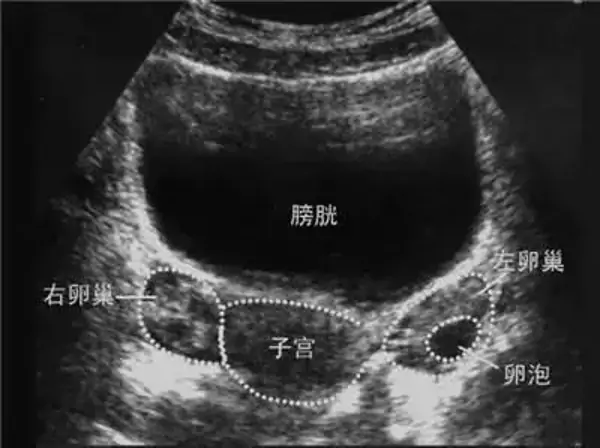

卵泡是由卵子及其周围的卵泡细胞组成,正常女性每个月都会有卵泡发育,能够发育成熟的就是我们所说的优势卵泡。一般来说女性朋友可以通过B超监测卵泡的生长,这时就可以判断是否有优势卵泡的发育了。

女性朋友可以通过B超监测卵泡的生长

正常周期中,在B超的影像图中,卵泡为边界清晰的圆形无回声区,从周期的第5~6天卵泡直径约为5~7mm,第10天时卵泡直径可达10mm,此时超声已能清晰显示。正常周期中卵泡发育的速度比较恒定,约1~3mm/d,最快可达4mm/d,愈临近排卵期,增长愈快,排卵前5小时可增长7mm。

B超下的卵泡